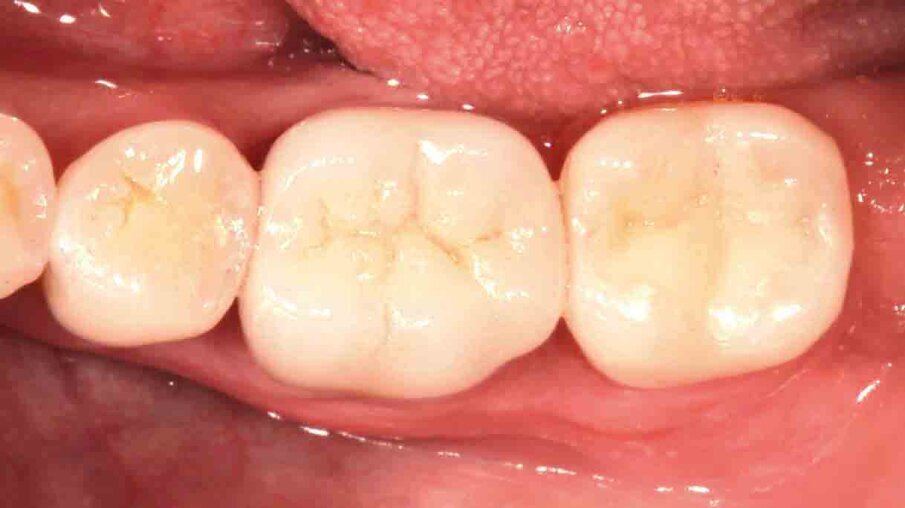

Fig. 10: Situation after crown placement, removal of the excess cement and thorough cleaning. The crown blends in nicely with the surrounding tooth structure.

Fig. 11: At the check-up several days after crown placement, a great overall picture is obtained. The patient is happy with the final restoration in terms of aesthetics and function.